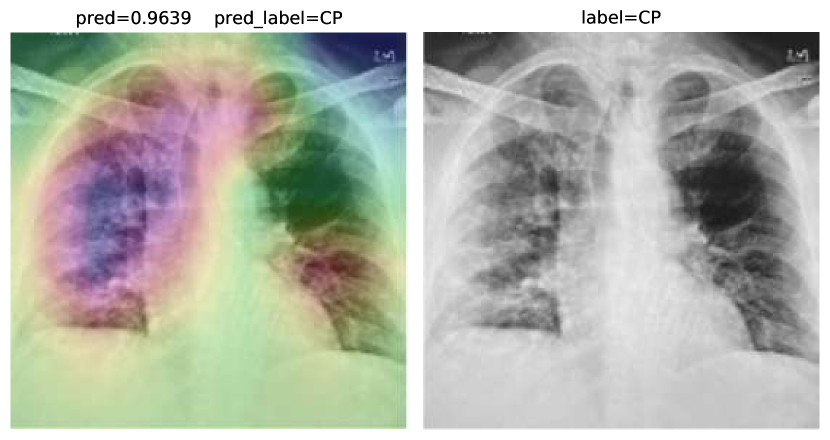

As an extra step, we expanded COVID-CXNet for multiclass classification between normal, COVID-19 pneumonia (CP), and non-COVID pneumonia to examine its performance regarding the differentiation between two types of pneumonia. CP is often appeared with bilateral findings, whereas non-COVID pneumonia or CAP mostly has unilateral consolidations. Since most images are collected from the CXR-14 dataset, a histogram matching is applied to adjust histograms according to a base image. The output layer is changed to have three neurons with the SoftMax activation function. Confusion matrix is shown in Table 4.

Accuracy score is 81.04%, with f-scores of 0.85 and 0.76 for CP and CAP classes, respectively. In a number of cases, especially in the first stages of virus progression, CP has unilateral findings. Also, CAP may cause bilateral consolidations. Therefore, some cases are expected to be misclassified between CP and CAP. From the confusion matrix, it could be seen that a relatively high number of images are misclassified between CAP and normal. A potential reason for this issue is considered to be related to wrong labeling. Besides, some CAP CXRs are from patients with early-stage disease development. To confirm the model performance, Grad-CAMs are plotted in Fig. 19.

Refer to caption

Figure 19: COVID-CXNet multiclass classification visualization results

The model is properly looking at one lobe for detecting CAP and both lobes for CAP and normal images. There are some wrong labels, nevertheless. A figure containing more visualizations is found in Appendix C. To further enhance statistical scores, a hierarchical approach is implemented. In the first level, we classify images into normal and pneumonia classes. In the second level, pneumonia images are categorized into CP and CAP. Final confusion matrix is illustrated in Table 5.